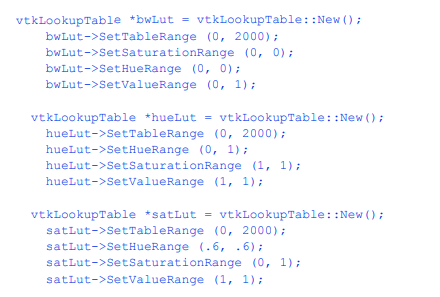

我们可以通过多种方式改进这种可视化。首先,我们可以为皮肤选择更合适的颜色(和其他表面属性)。我们使用vtkProperty方法SetDiffuseColor()将皮肤颜色设置为肉色。我们还在皮肤表面添加了一个镜面组件。接下来,我们可以添加与各种解剖特征相对应的额外等值面。这里我们选择通过添加额外的管道段来提取骨表面。它由筛选器vtkMarchingCubes、vtkPolyDataMapper和vtkActor组成,就像我们对皮肤所做的一样。最后,为了提高系统的渲染性能,我们从输出中创建三角形条

轮廓的过程。这需要添加vtkStripper。图12 - 3显示了生成的图像,下面是该管道的c++代码。